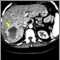

A hepatic hemangioma is a noncancerous liver tumor made of widened (dilated) blood vessels.

A hepatic hemangioma is the most common noncancerous tumor of the liver. It is believed to be a birth defect.